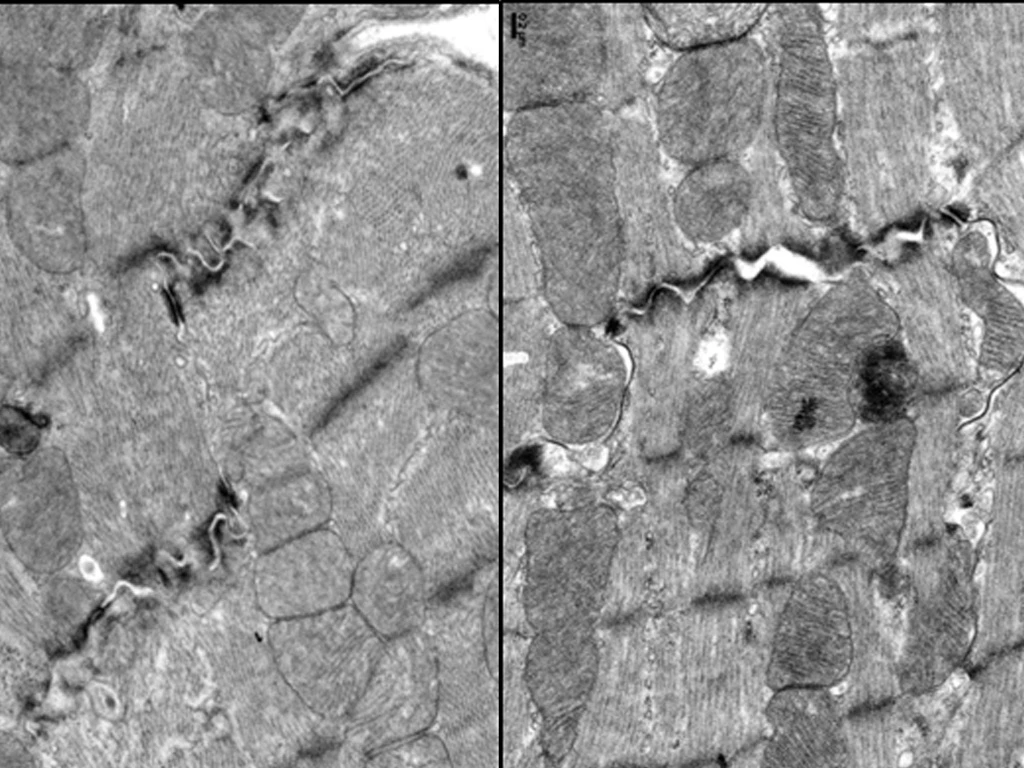

蔡亭芬指出,CISD2長壽基因的表現在心臟會隨著年齡而下降,CISD2對心臟功能的維持非常重要。研究發現,小紅莓會抑制心肌細胞中長壽基因CISD2的表現,使粒線體與鈣離子調控失衡,導致心臟收縮與節律出現問題,相反地,橙皮素可以重新啟動長壽基因CISD2,減少心肌細胞受損。

令人振奮的是,橙皮素不僅能撐起心臟保護傘,在動物實驗中,小紅莓處理的長腫瘤小鼠,注射橙皮素後,不僅顯著改善心臟功能,腫瘤體積也明顯縮小,顯示橙皮素不會影響小紅莓的抗癌力。橙皮素對心肌細胞的保護作用,研究團隊也運用由美國史丹福大學所提供的人類誘導性多能幹細胞(iPSC)衍生的心肌細胞加以驗證,強化支持橙皮素臨床應用的潛力。